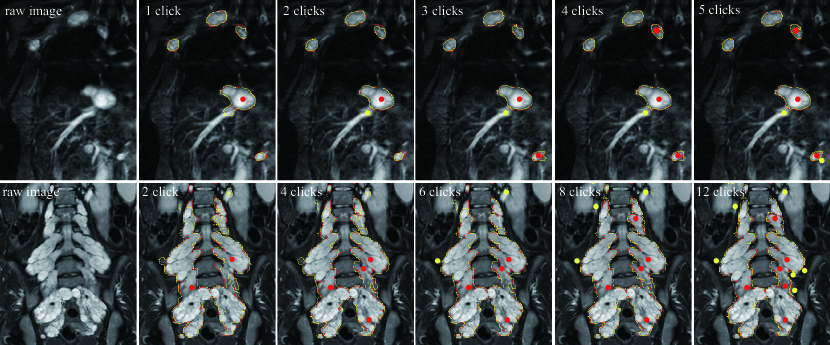

V-D Interactive results

Two interactive segmentation results of plexiform neurofibromas with DINs are displayed in Fig. 9. The ground truth contours (manual segmentation) are red, and the prediction contours are yellow. The positive and negative interactive clicks are marked by red and yellow points, respectively. DINs achieve accurate segmentation of multiple tumors with one click and iteratively improves segmentation with additional interactions. Notice that the is set to by default, which is suitable for most neurofibroma segmentation situations.